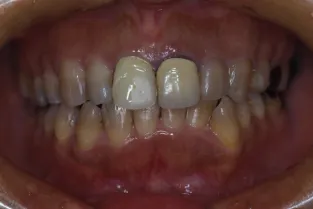

初診時

治療完了時

| 患者様のお悩み | 外傷で歯が抜けた |

| 治療法・使用素材 | インプラント治療の後、セラミック治療 |

| 患者様の年代 | 20代 |

| 治療開始年齢 | 20代 |

| 治療にかかった期間 | 8か月 |

| 性別 | 女性 |

| この治療のリスクについて | インプラントが正しい位置に入るかどうか |

| 治療にかかった費用 | 45万円 |